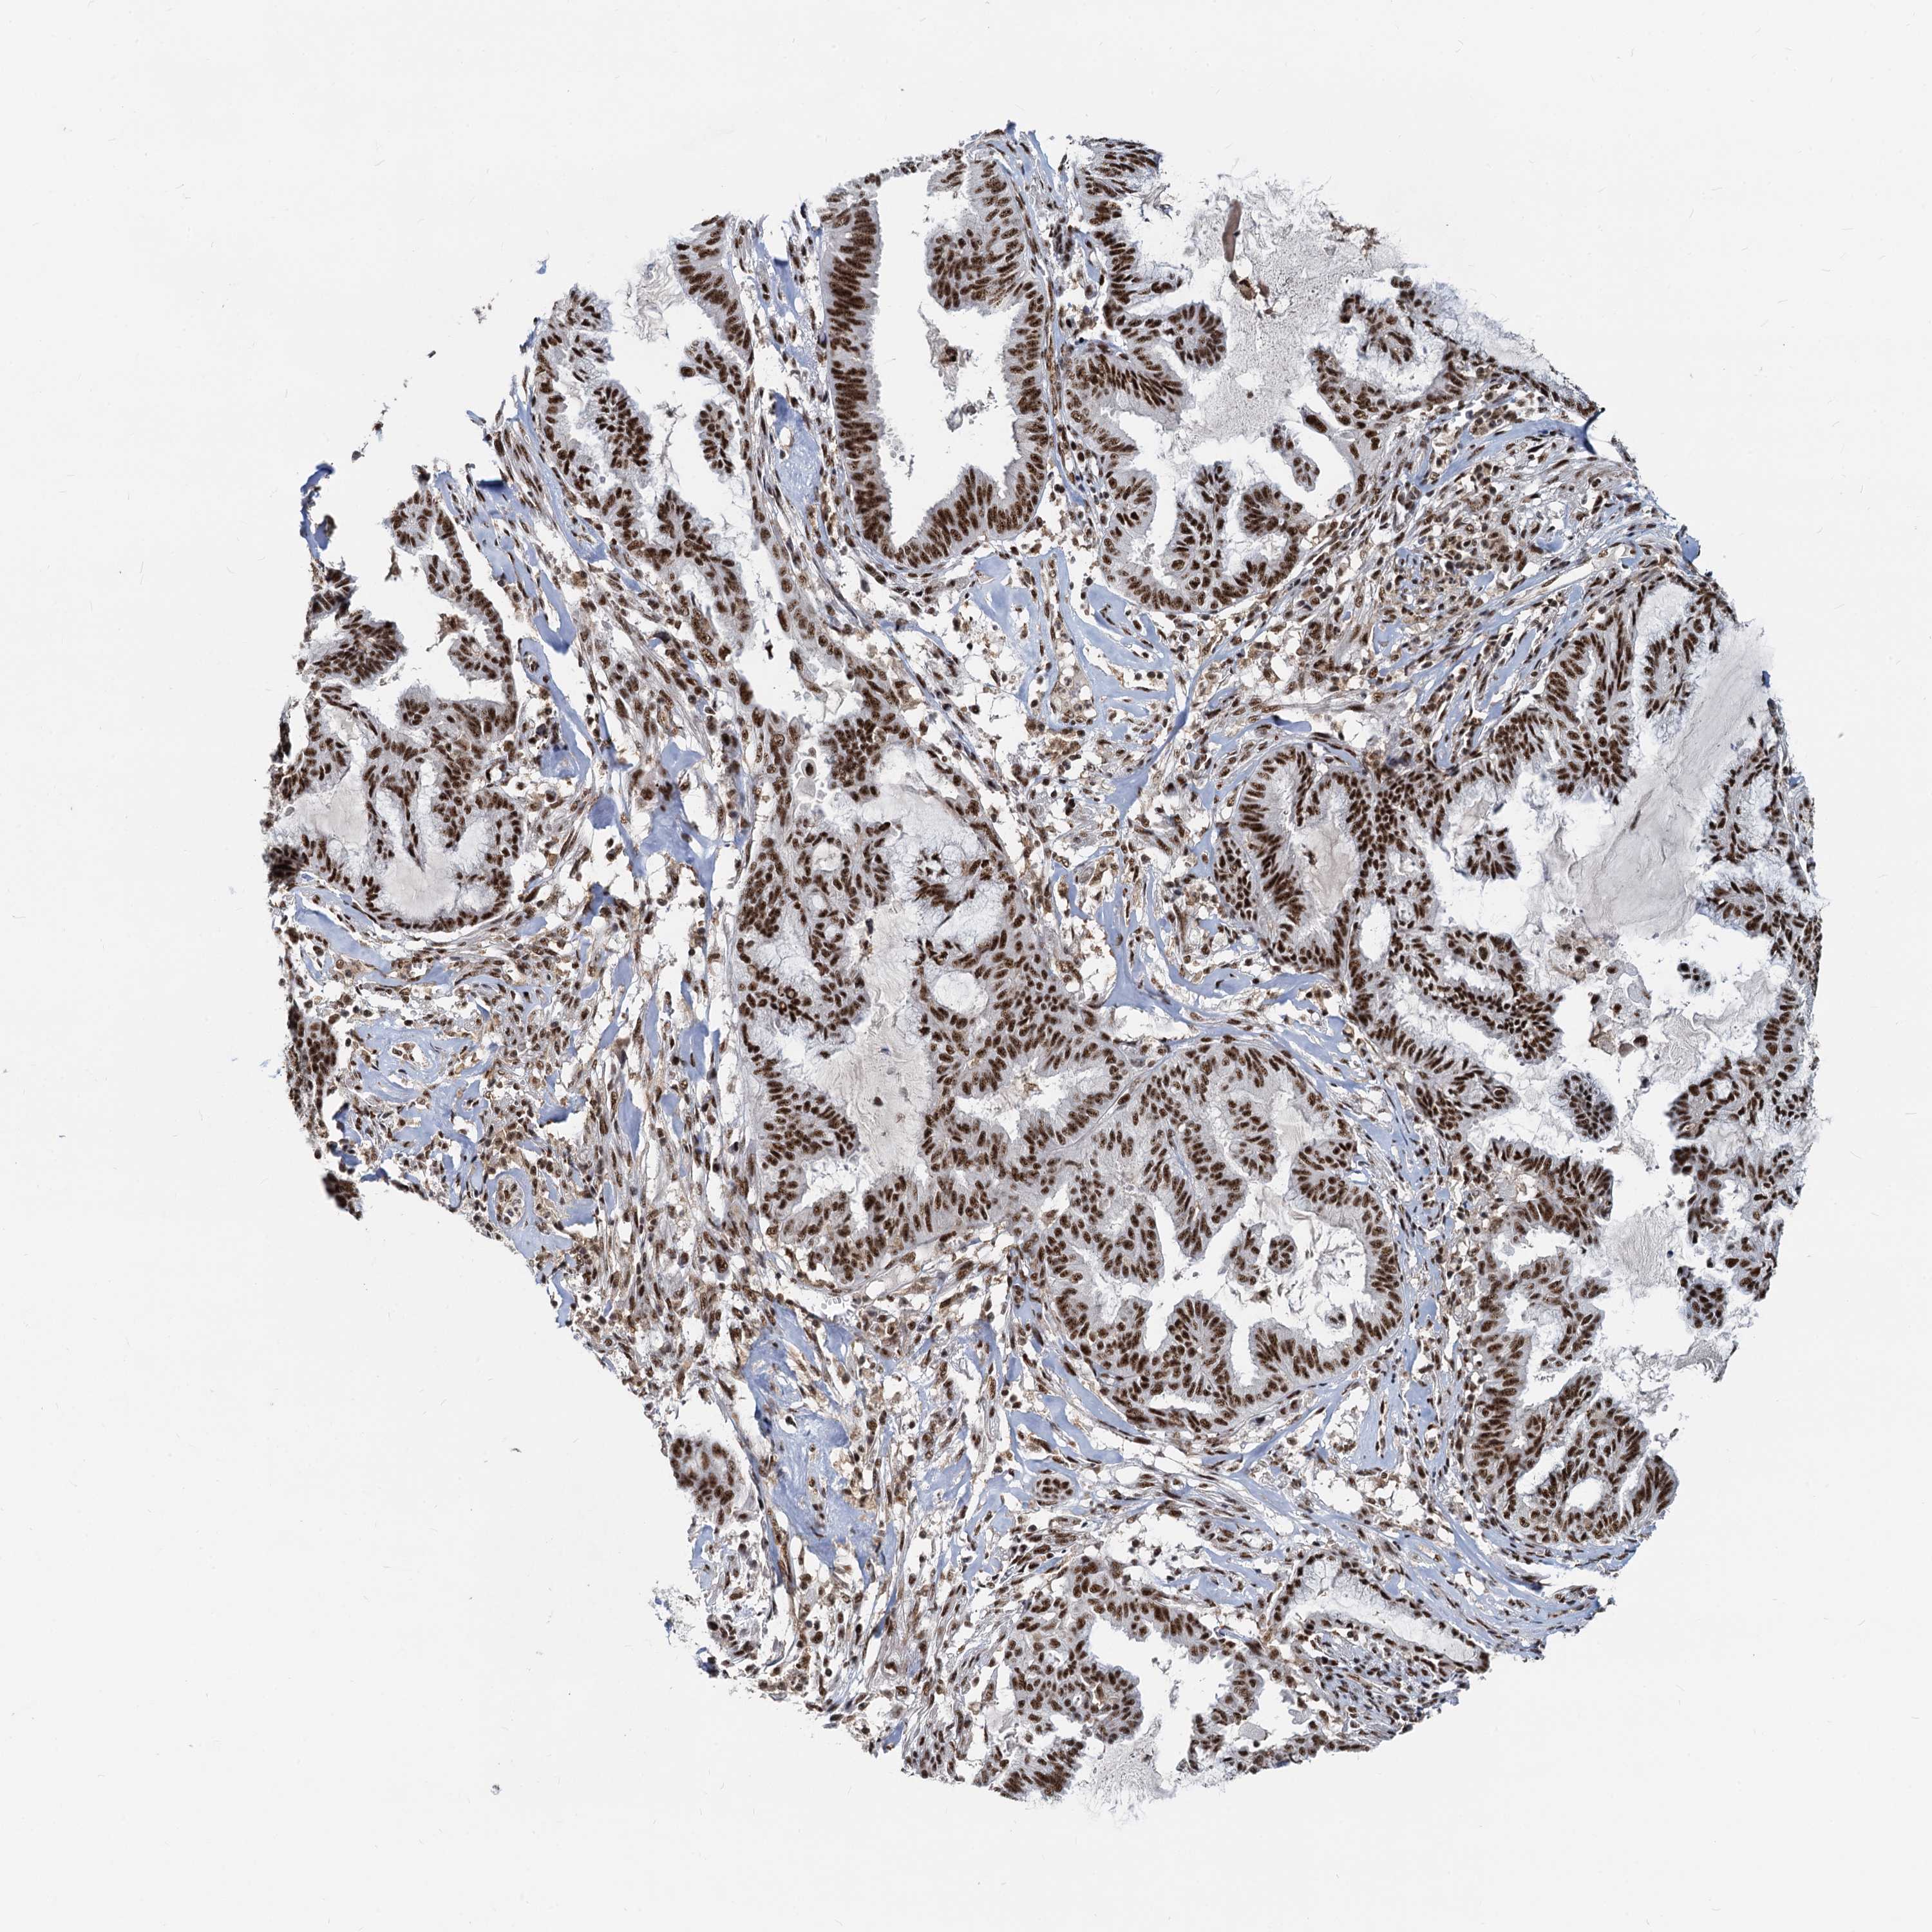

ENDOMETRIAL CANCER - Protein expressioni

A mouse-over function shows sample information and annotation data. Click on an image to view it in a full screen mode. Samples can be filtered based on level of antibody staining by selecting one or several of the following categories: high, medium, low and not detected. The assay and annotation is described here.

Note that samples used for immunohistochemistry by the Human Protein Atlas do not correspond to samples in the TCGA dataset.

Antibody stainingi

Antibody staining in the annotated cell types in the current human tissue is reported as not detected, low, medium, or high, based on conventional immunohistochemistry profiling in selected tissues. This score is based on the combination of the staining intensity and fraction of stained cells.

Each image is clickable and will lead to virtual microscopy that enables deeper exploration of all samples and also displays staining intensity scores, fraction scores and subcellular localization as well as patient and tissue information for each sample.

Antibody HPA040252

Staining

High

Medium

Low

Not detected

Intensity

Strong

Moderate

Weak

Negative

Quantity

>75%

75%-25%

<25%

None

Location

Nuclear

Cytoplasmic/membranous

Cytoplasmic/membranous,nuclear

Adenocarcinoma, NOS

Adenocarcinoma, metastatic, NOS